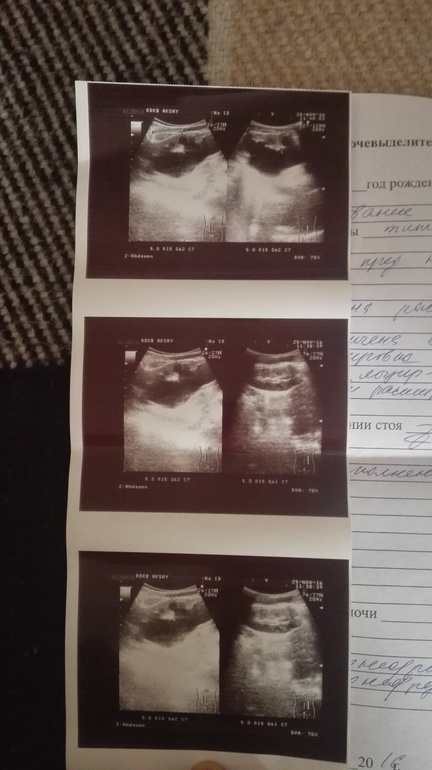

Добрый день подскажите как быть с нашим узи

Здравствуйте. Одно УЗИ не определяет тактики лечения, это всего лишь оценочная методика. Ребенка необходимо обследовать в полном объеме, с выполнением контрастных исследований, лабораторных и т.д. Только тогда можно говорить о каком либо прогнозе. Врач УЗИ не может ставить в заключении диагноз хронический пиелонефрит, он может только описать характер видимых изменений.

Мне сложно оценивать ситуацию заочно, но из представленных данных я не вижу результатов свидетельствующих о неработающей почке. Результаты экскреторной урографии или нефросцинтиграфии есть?

ОАМ и ОАК показывают хороший результат на снимках отсроченого ренгена большие полости внутри почки и тонкая перенхима, весной была операция по сужению мочеточника, а сейчас уролог говорит что почка не работает и нужно удалять.